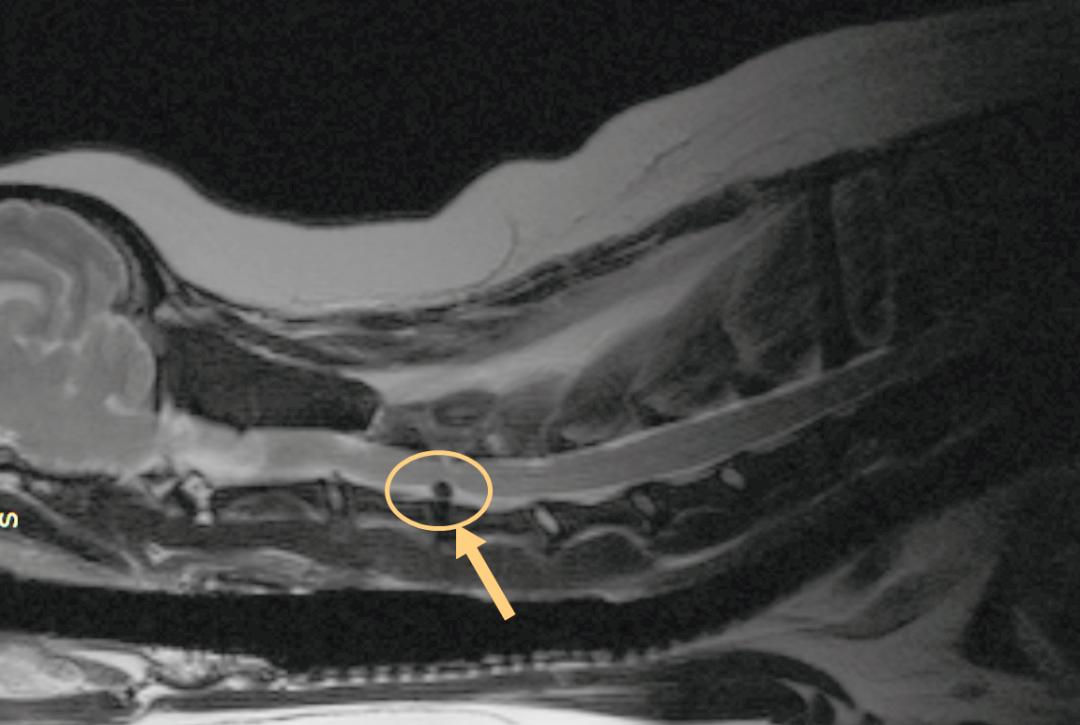

在刘光辉医生的推荐下,Mimi来到瑞鹏宝安中心医院做进一步会诊。宝安中心李晓坤医生随即为狗狗进行MRI检查。结果显示,狗狗C3—C4椎体出现颈椎间盘脱出。正是这小小的“脱出”,让Mimi承受巨大的疼痛!

图中画圈部分是C3-C4椎体出现椎间盘脱出的地方